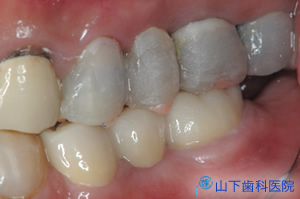

| 咬み合せの状態がよく、左右均等に何でも噛めて、不安なくなり、体調もよくなったとご満足頂いています。 | ![]() ![]() |

| 前歯のブリッジは、下から付き上げを食らわず、ぐらつかなくなりました。露出した歯根をコンポジットレジンでマスキングして経過を診ています。 | ![]() |